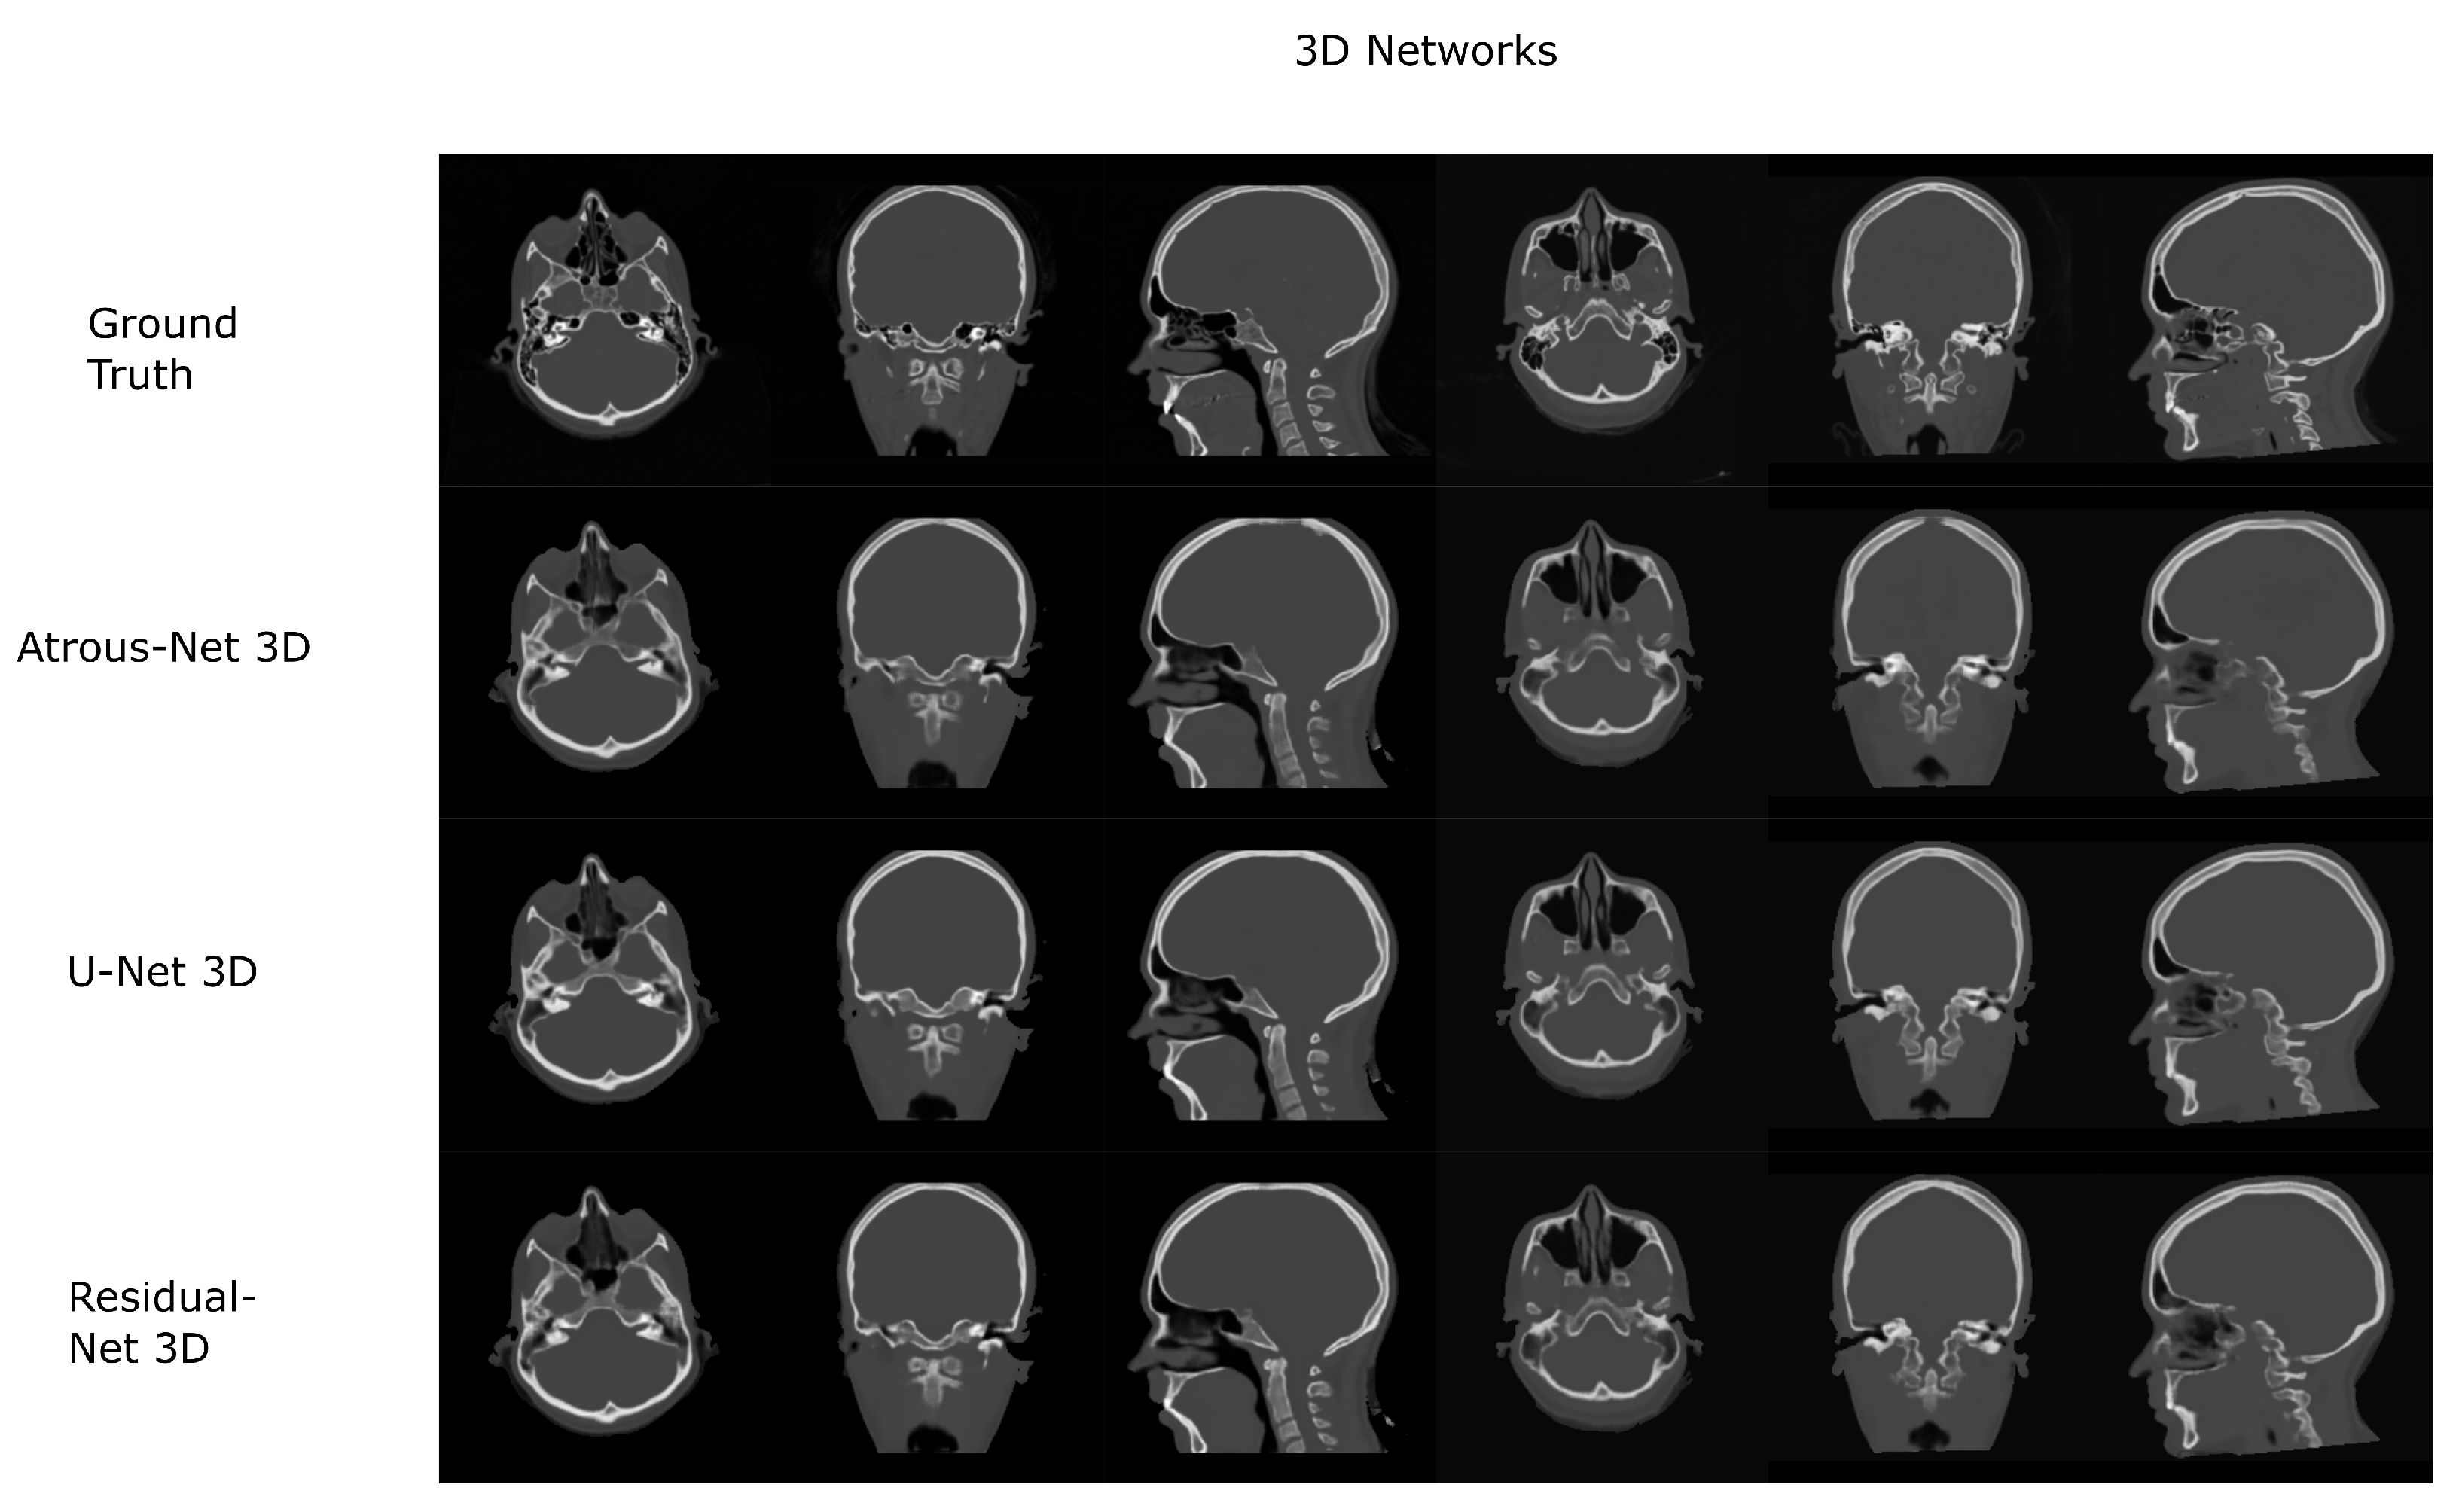

Figure 7. Head results using 3D-16 networks.

3.1. Head Dataset Results

The results for all tissues using the head dataset are depicted in Table 1, Table 2 and Table 3; the results using only the bone voxels are detailed in Table 4, Table 5 and Table 6; the results using only the fat voxels are detailed in Table 7, Table 8 and Table 9; and the results using only the soft-tissue voxels are detailed in Table 10, Table 11 and Table 12. The best performing 2D network for the head dataset was the Residual-net. The results presented a MAE of 99.83 HU, a PSNR of 24.83 and a Pearson Coefficient of 0.931 in all tissues, and a MAE of 326.33 HU, a PSNR of 19.04 and a Pearson Coefficient of 0.826 in bone voxels. The ANOVA test revealed a statistically significant effect of the 2D architectures for MAE results (all tissues: F 2 , 36 = 91.1 , p < 0.001 ; bone: F 2 , 36 = 74.2 , p < 0.001 ) and PSNR results (all tissues: F 2 , 36 = 99.3, p < 0.001 ; bone: F 2 , 36 = 85.6, p < 0.001 ). A paired t-test was used to compare the Residual-net to the other networks reporting also statistically significant differences in the MAE and in the PSNR (Table 13). Using 2D convolutions, the Atrous-net and the U-net performed 5% and 18% worse than the residual-net, respectively. Moreover, the U-net network was clearly behind the other networks using 2D convolutions. Nevertheless, the U-net in 3D-16 obtained a MAE of 89.54 HU, a PSNR of 25.69 and a Pearson Coefficient of 0.943 in all tissues, and a MAE of 289.10 HU, a PSNR of 20.05 and a Pearson Coefficient of 0.861 in bone voxels, which were the best results for the head dataset. The ANOVA test also reported a statistically significant effect of the 3D networks for the MAE (all tissues: F 2 , 36 = 63.2 , p < 0.001 ; bone F 2 , 36 = 189.8 , p < 0.001 ) and the PSNR (all tissues: F 2 , 36 = 10.5 , p < 0.001 ; bone: F 2 , 36 = 83.1 , p < 0.001 ). The post hoc paired t-test that is depicted in Table 14 also reported statistically significant differences in the MAE and PSNR after comparing each architecture. Summarizing, the results using 3D convolutions from the U-net were 17% and 10% better than those of the Atrous-net and Residual-net, respectively. Visual result examples of head pseudo-CTs are depicted in Figure 6 and Figure 7. Table 15 shows the time needed to synthesize a whole head volume using the different architectures.